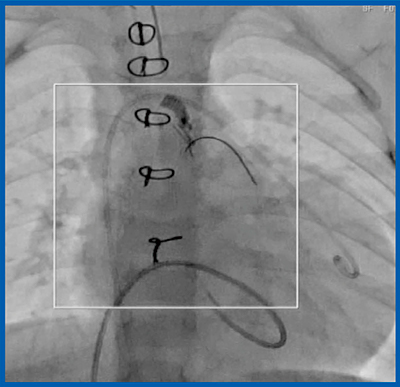

見えない被ばくを可視化することで線量マネージメントを可能にする“Dose Tracking System”は,術中の患者の入射皮膚線量をリアルタイムにモニタリングし,入射皮膚線量の度合いを仮想患者モデル上にカラーマップで表示する(図8)。また,術者被ばくを低減する“Spot Fluoro”は,手技中に必要な範囲にのみX線を照射する機能である。例えば,全面照射を100とした場合の散乱線量(距離50cm,高さ150cm)は,面積が1/4では52%,1/9では34%となる。修正大血管転位症の肺動脈絞扼術後にプレッシャーワイヤによる肺動脈圧の評価を行った例では,プレッシャーワイヤが挿入された部分のみにSpot Fluoroを使用すると,X線の照射面積は全面照射の約1/4となり(図9□),放射線量が大幅に抑制される。Spot Fluoroの使用には若干の慣れが必要であるが,手技中に実際に見ているのは限られた範囲のみであり,また,照射範囲は自由に変更可能である。

図9 Spot Fluoro